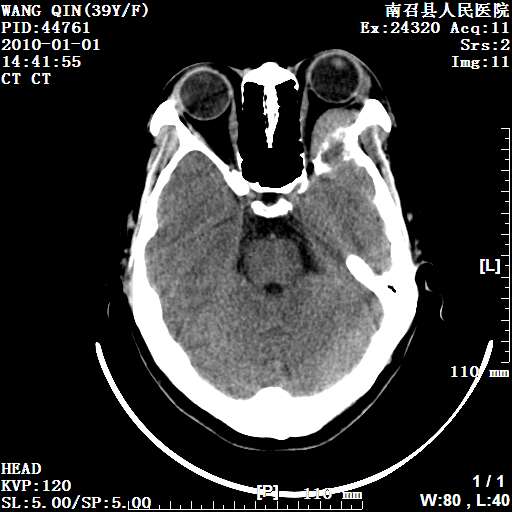

以下是引用随光逐影在2010-1-22 9:03:00的发言:[br]考虑左侧中颅窝(蝶骨翼区)脑膜瘤侵犯蝶骨翼并突入左侧眼眶。

以下是引用水过无痕在2010-1-22 14:55:00的发言:[br]一、定位:颅外占位;二、定性:恶性可能性大;三、组织来源:来源于左侧眼外直肌或其他部位;考虑为:横纹肌肉瘤>转移瘤>脑膜瘤.